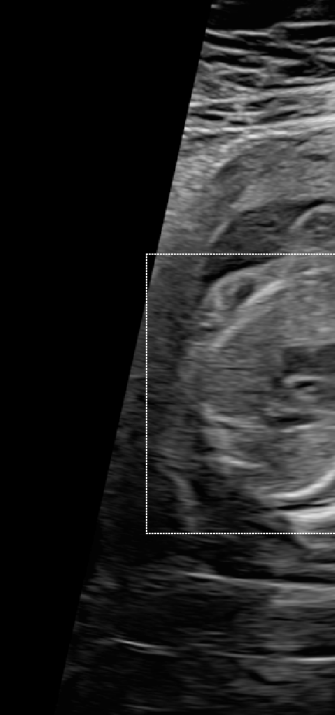

Three in vivo Bmode fetal images with and without aberration correction are presented in Figs. 10-12. GIF images of examples A-L (see Fig. 9 and Table 5) alternating between the corrected and uncorrected images are uploaded as supplementary material. The differences in image quality are easier to appreciate in the GIFs than in a side-by-side comparison. The data points for the three examples are colored black in Fig. 9. Table 5 give tabular values for the global sound speed estimate, sharpness increase (κ𝜅\kappa) and answers from the clinical evaluations.

Refer to caption

(a) Uncorrected Bmode.

(b) Aberration corrected Bmode.

(c) Uncorrected Bmode.

(d) Corrected Bmode.

Figure 11: Example B. In vivo fetal Bmode image using constant 1540 m/stimes1540dividemetersecond1540\text{\,}\mathrm{m}\text{/}\mathrm{s} and the estimated average sound speed map. The average sound speed map is shown in the top right corner and the rightmost colorbar indicates the sound speed values. Alternating GIFs are found in the supplementary material.

The in vivo examples A-C, in Figs. 10-12 respectively, show different nuances of how sound speed aberration correction improves focusing quality. A noticeable improvement in Fig. 10 is the improved contrast and clarity of borders. The sound speed correction seems to remove the double structure indicated by the arrows in Figs. 10c-10d. The skull border and the brain structures in Fig. 11 are also better defined and clearer after aberration correction. Example C in Fig. 12 is the image with the highest increase in Tenengrad κ𝜅\kappa, seen from Fig. 9 and Table 5. The improvement in image quality is evident around the boundary of the fetus body and the correction sharpens the structures indicated by the arrows. The improved contrast between the layers in the shallow tissue layers is also noticeable.